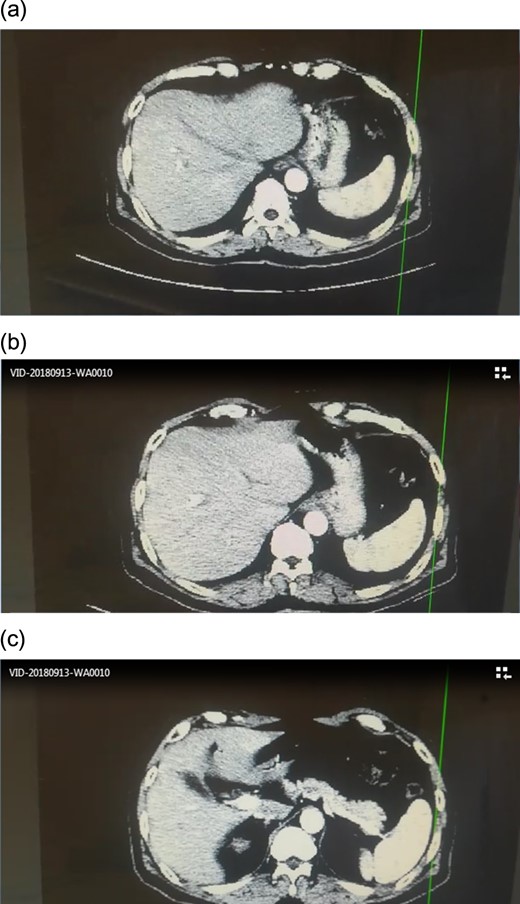

In operating room, Kocher incision, no ansarca, no peritoneal metastasis, the decision to perform whipple procedure was made. Gallbladder was resected, kocher maneuver, when isolating the CBD and common hepatic artery, anomalies were found, and the artery system was not that clear, no clear celiac trunk and no clear common hepatic artery. (Fig. 2)

Angiographic CT after procedure confirmed the absence of celiac trunk, the absence of left gastric, the splenic artery arising from aorta directly and common hepatic artery arising from superior mesenteric artery.(Fig. 3)